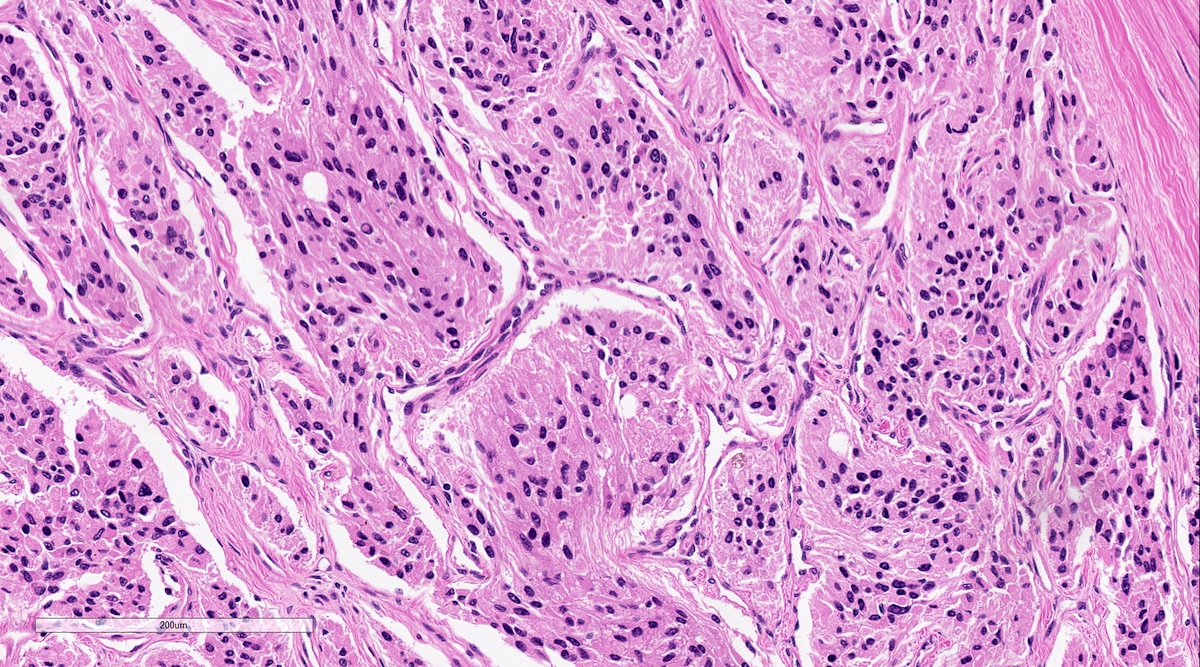

Microscopic (histologic) description

- Prevailing histologic pattern: epithelioid chief cells arranged in distinctive clusters / nests (zellballen pattern), separated by prominent fibrovascular stroma (J Clin Med 2018;7:280)

- Trabecular pattern: ribbons or cords of epithelioid cells divided by fibrous bands

- Other patterns: pseudorosette, angioma-like, spindled and sclerosing

- Chief cells: round, oval to polygonal cells with abundant granular basophilic, eosinophilic or amphophilic cytoplasm (Surg Pathol Clin 2019;12:951)

- Intracytoplasmic hyaline globules may be present in sympathoadrenal paragangliomas

- Giant multinucleated cells and bizarre cells can be present (Srp Arh Celok Lek 2002;130:7)

- Rarely, elongated and spindle shaped cells with a sarcomatoid appearance may be found

- Scattered ganglion cells can be seen

- May have nuclear atypia

- May have dysmorphic vessels, melanin-like pigment (neuromelanin) (pigmented paraganglioma), amyloid, abundant stroma and osseous metaplasia (Diagn Pathol 2012;7:77, Hum Pathol 1992;23:33)

- No or rare mitotic figures except in highly aggressive rapidly proliferating lesions

- May have focal chronic inflammatory infiltrate

- Necrosis is unusual except in patients who have undergone preoperative tumor embolization

- Special histopathologic features usually related to genetic syndromes:

- VHL syndrome: prominent stromal edema, clear cytoplasm and lipid degeneration (Am J Surg Pathol 1987;11:480)

- SDHx related syndrome: granular eosinophilic cytoplasm (Am J Surg Pathol 2020;44:422)

- MEN2 syndrome: unilateral or bilateral adrenal medullary hyperplasia (Neoplasia 2014;16:868)

Microscopic (histologic) images

Contributed by Luvy Delfin, M.D. and Sylvia L. Asa, M.D., Ph.D.